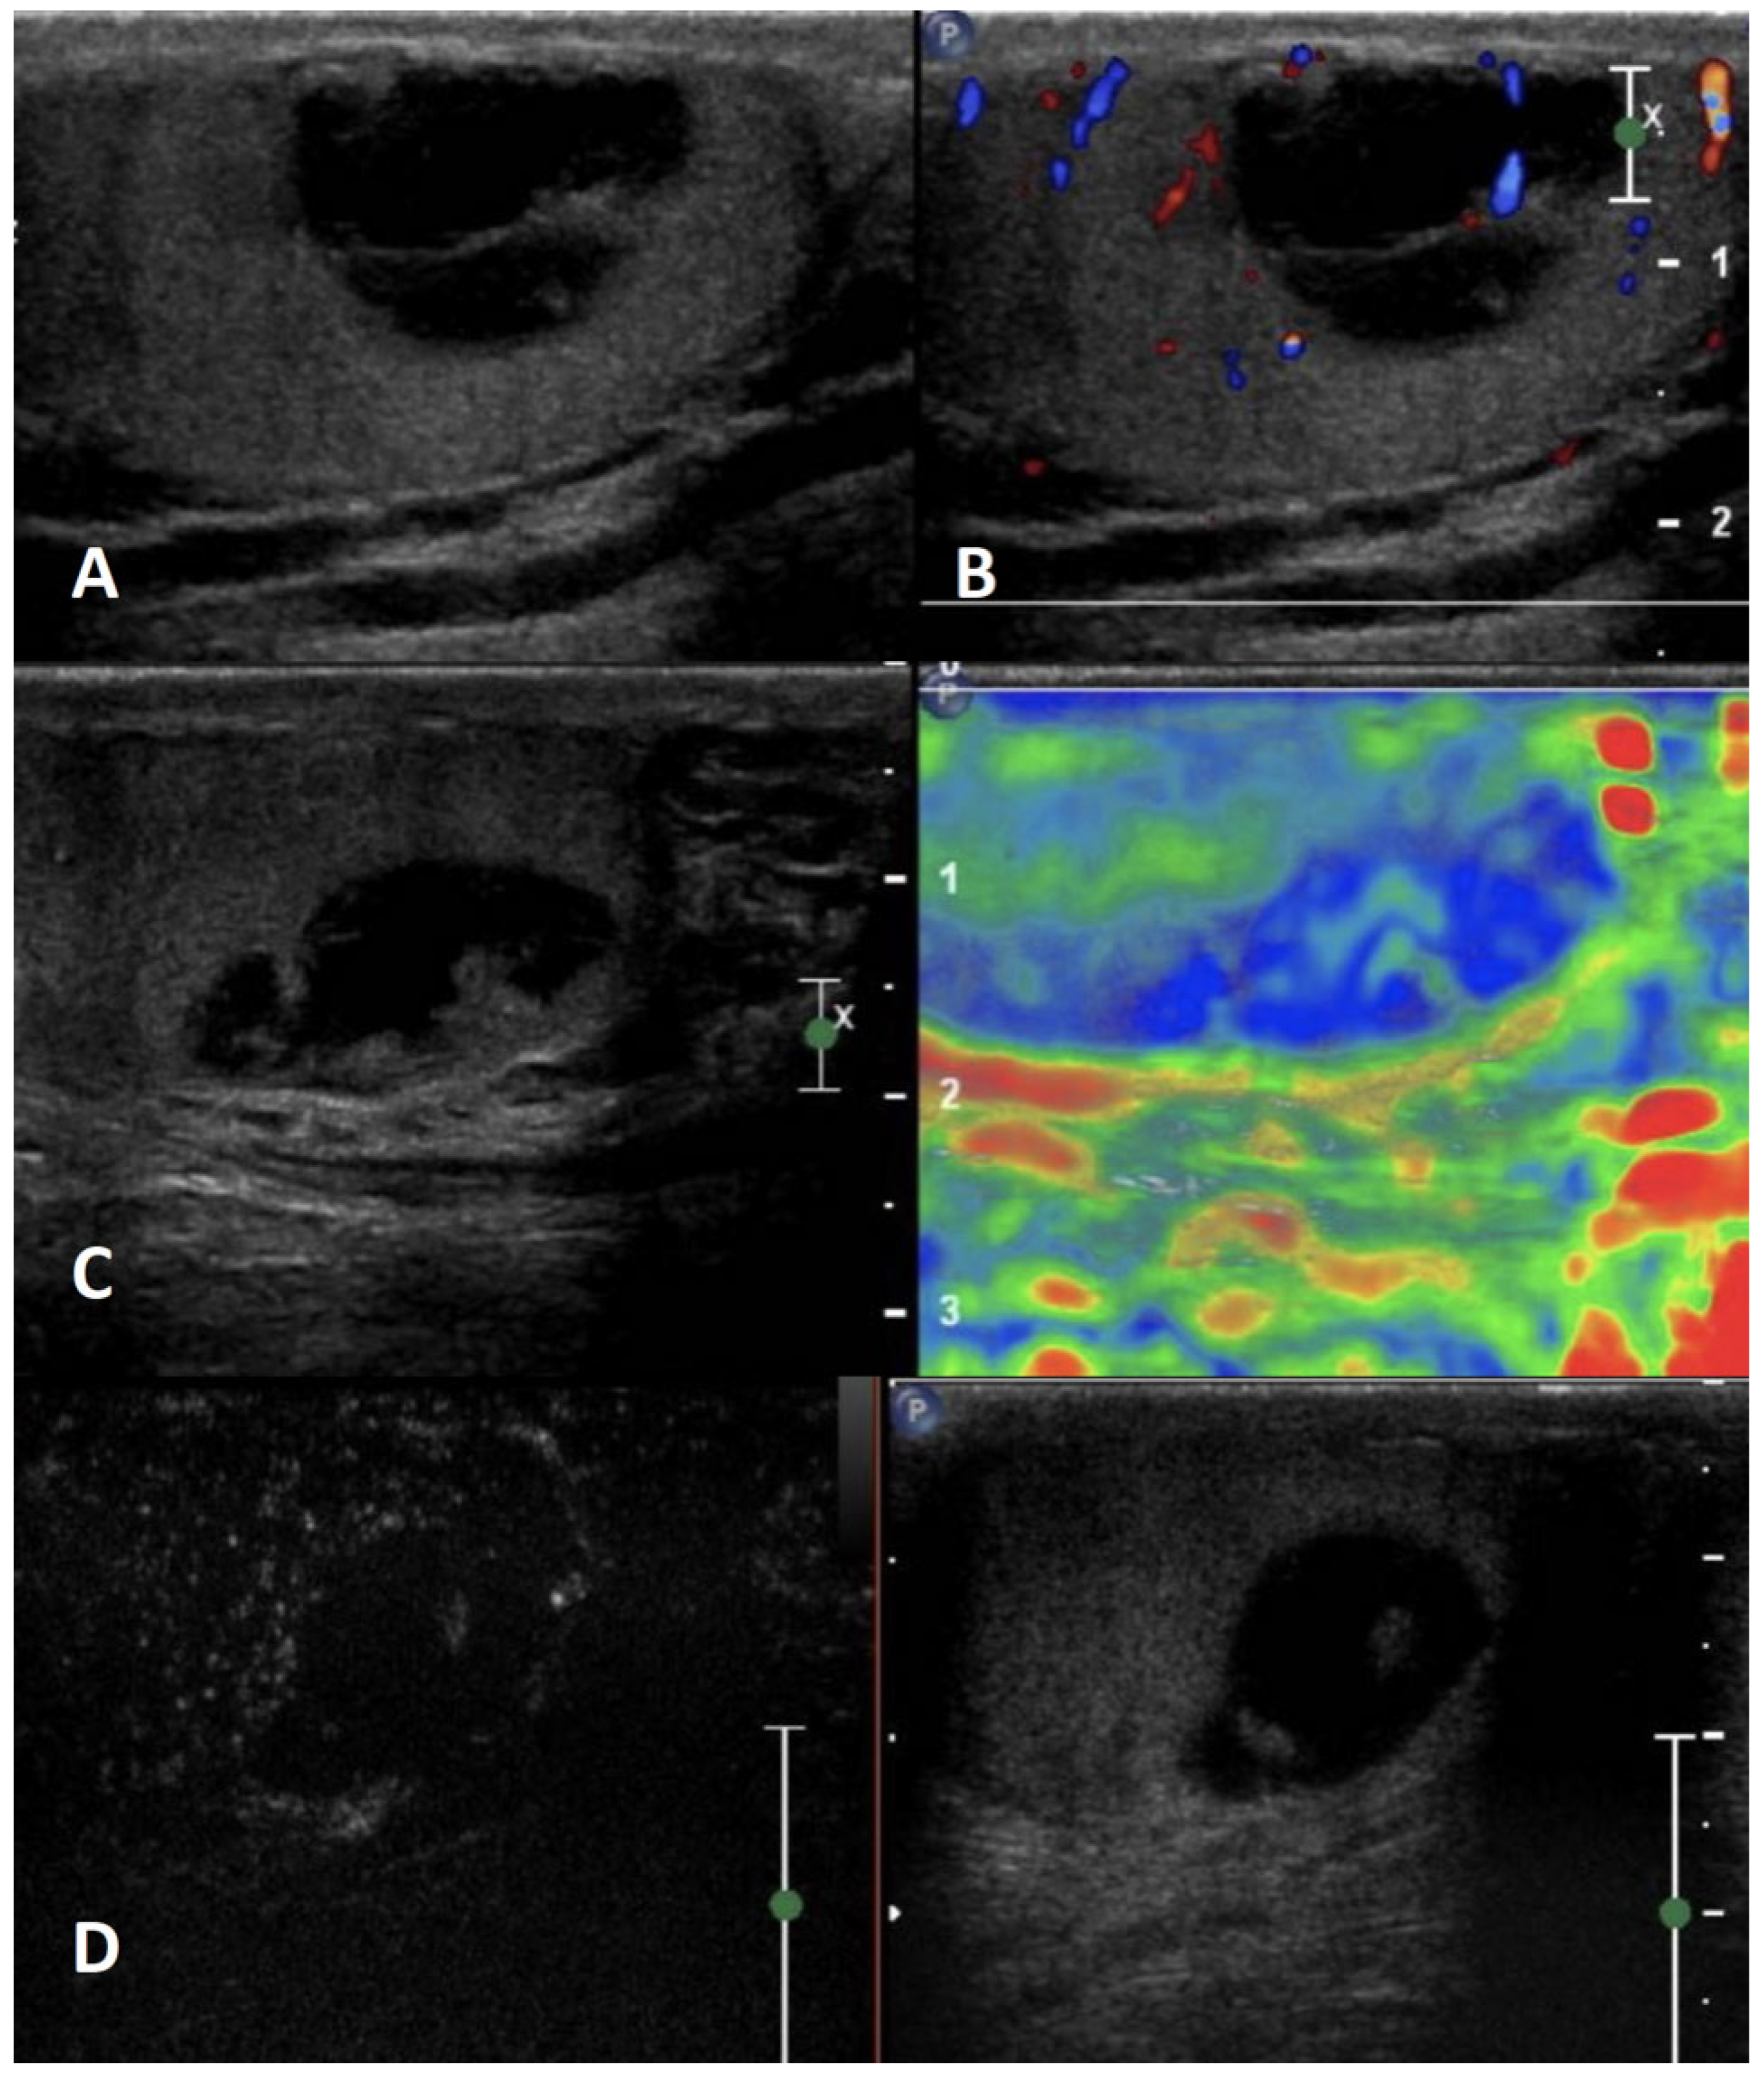

5.3.1. Leydig Cell Tumor (LCT)

| Leydig cell tumor | Generally asymptomatic; it can produce androgens | Negative | Hypoechoic, homogeneous well-demarcated lesion (possible hyperechoic halo) | Hypervascularized | Homogeneously hyperenhanced (rapid wash-in, delayed wash-out) | Hard lesions with low/absent elastic strain |